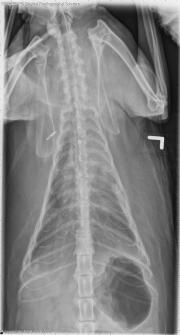

These radiographs are of a 9-year-old cat with labored breathing and panting. What are your differential diagnoses?

There is increased soft tissue opacity within the thorax, with retraction of the lung lobes and evidence of fissure lines. A few small gas bubbles are visible in the pleural space, secondary to thoracocentesis. The cardiac silhouette is obscured on the dorsoventral projection, but appears normal in size on the ventrodorsal projection. There is increased opacity and decreased volume of the left cranial lung lobe. A pulmonary nodule is also evident overlying the left side of the cardiac silhouette. Ill-defined nodules are present in the right caudal lung lobe.

• Pulmonary mass (primary pulmonary neoplasia, granuloma)

• Possible metastatic disease or diffuse granulomatous disease

• Secondary pleural effusion and atelectasis

• Adenocarcinoma with intrapulmonary metastasis

• Chronic proliferative pleuritis and pleural fibrosis and atelectasis, secondary to pleural effusion